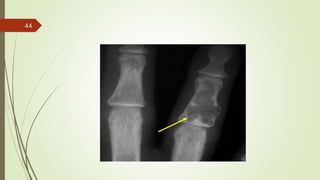

Imaging studies

 X-ray : osteolytic area of destruction with a permeative or moth-eaten appearance.

43

44